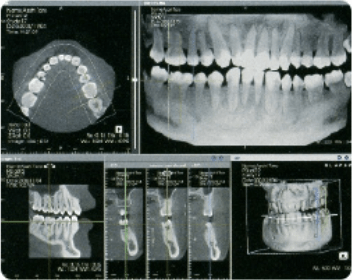

最新の歯科用CT

インプラント、矯正歯科での顎骨や歯の傾きの状態等の歯科治療・診断に大変有効です。

三次元の高画質画像を用いることで、断層方式パノラマエックス線撮影法や口内法エックス線撮影法では判別できない、

痛みや症状の原因の解析にも役立ちます。

レントゲン室で撮影した画像を3D画像として映像化

レントゲン室で撮影した画像を最新技術により正確でクリアな3D画像として映像化します。

顎関節や奥歯など、様々な角度からお口の中を確認できます。